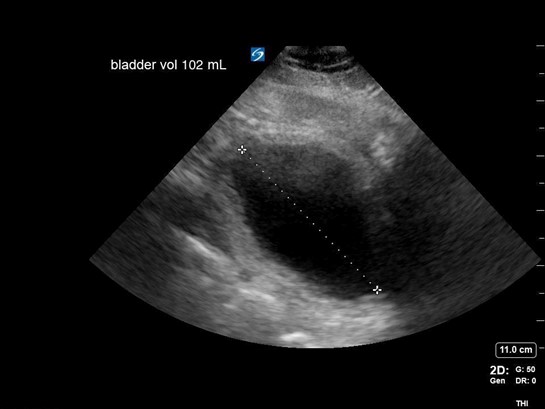

A 65-year-old male with a history of HTN, BPH, IDDM, and lumbar spinal stenosis presented to the ED with low back pain and lower extremity weakness. He denied fever, abdominal pain, and dysuria. He reports that he is able to urinate but unable to state if his urinary frequency has increased beyond “my normal prostate issues.” He notes he has fallen twice because “my legs just seem to give out on me.” On physical exam, he demonstrates 4+/5 bilateral LE strength, mild distal sensory loss, and absent patellar and Achilles reflexes. His rectal tone was equivocal. After use of a urinal, bedside POCUS was used to measure his post-void residual bladder volume:

Figure 3. Calculation of bladder volume using the ellipsoid method (L x W x H x 0.52 = mL)

Findings concerning for Cauda Equina were all present in this patient’s history, physical exam, and workup. Current literature defines normal post-void bladder volume in adults as < 50 mL in patients under 65 years of age, and < 100 mL in those older than 65. Two hundred milliliters or greater is generally regarded as the threshold for retention.1 In this case, the patient was just on the cusp of normal vs abnormal post-void urinary volume, but with his other clinical signs and symptoms, warranted emergency spine consultation and MRI. Imaging eventually showed severe compression of the spinal nerve roots by discs at the L2-3 and 3-4 levels, necessitating emergent decompression.

With the patient in supine position, a 2- to 5-MHz curvilinear probe is placed above the patient’s symphysis pubis in the midline position. To obtain a cross-sectional view of the bladder, the probe is oriented with the marker towards the patient’s right side. Once an image is obtained, the probe can be rotated 90 degrees to orient the marker towards the patient’s head for a long or sagittal view of the bladder. Bladder volume is obtained using the ellipsoid formula of depth x width x height x 0.52 (correction factor). Normal bladder findings include a smooth wall measuring 3-5 mm, which may decrease to 2-3 mm when filled. As discussed above, normal post-void residual volume in patients < 65 yo is < 50 mL and < 100 mL in those over the age of 65. A post-void residual of > 100 should raise suspicion about a mechanical, pharmaceutical, or neurogenic cause of retention.2-7